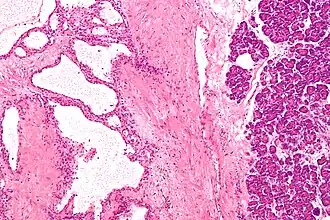

| Micrografia de um cistoadenoma seroso do pâncreas; coloração H&E. | |

Cistoadenoma seroso do pâncreas é um tumor benigno do pâncreas. Geralmente situa-se na cabeça do pâncreas,[1] e pode estar associado com a síndrome de von Hippel-Lindau.[2] Ao contrário de outros tumores císticos do pâncreas, as neoplasias císticas serosas são quase sempre beningnas, embora existam casos raros de cistoadenocarcinomas serosos malignos.[3]